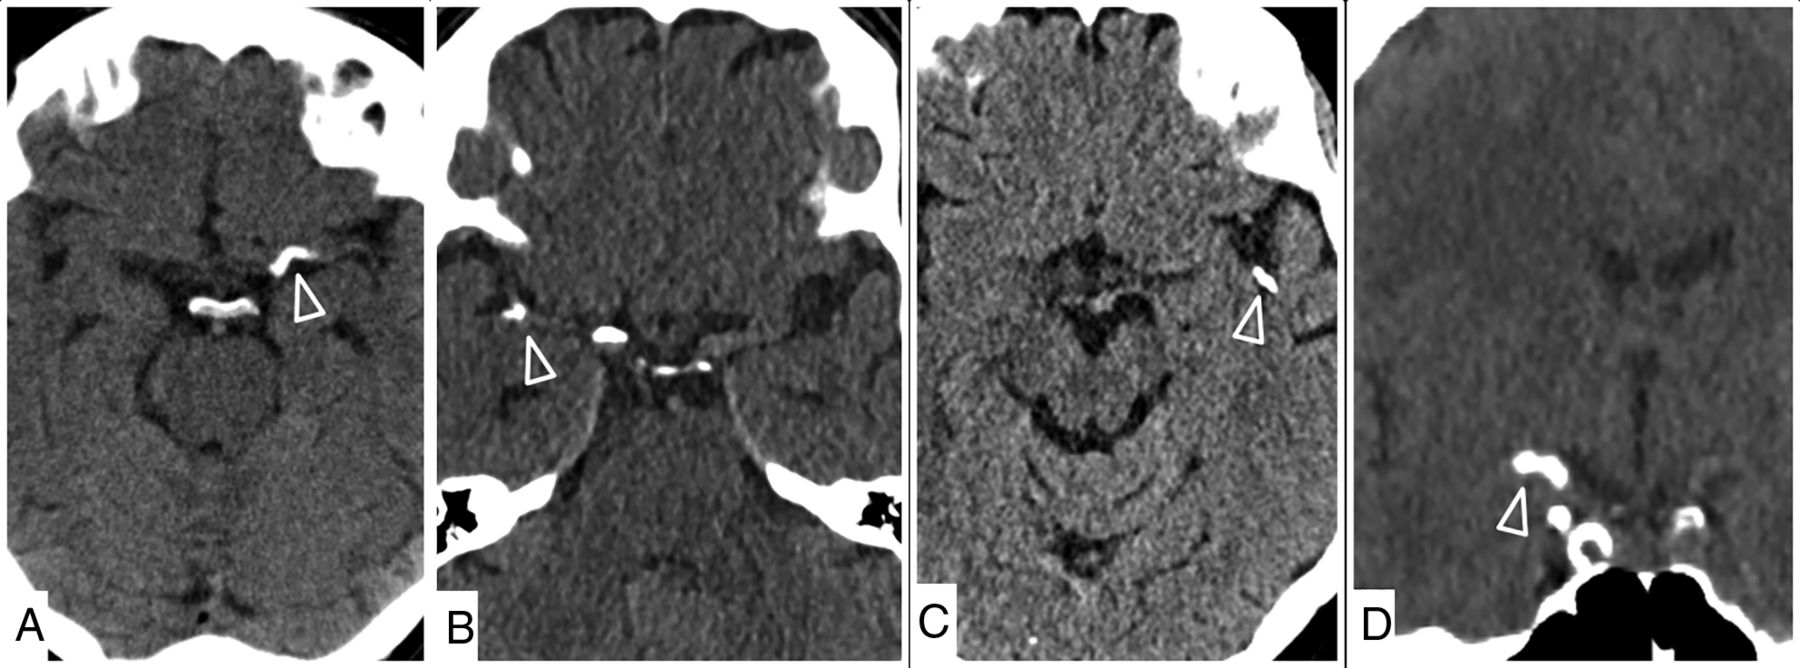

The mean maximal density of the thrombus was 327 HU (range, 150-1200 HU), and the mean thrombus length was 9.2 mm (range, 4–20 mm). The presumed source of embolization was unknown in 37.5% (15/40), cardiac in 17.5% (7/40), aortic arch in 15% (6/40), and ICA in 30% (12/40). Four patients had multiple calcified emboli, and 2 patients had an embolic event during an endovascular intervention (transcatheter aortic valve implantation and repair of an infrarenal aortic aneurysm). Extracranial calcification was most prominent at the carotid bifurcation and the aortic arch. The mean CLASS score was 1.1 (range, 0–2.5). Table 2 summarizes the occlusion site and clot properties. The Figure gives examples of intracranial calcified clots.

Examples of calcified emboli (arrowheads) in the left M1 (A), right middle cerebral artery bifurcation (B), left M2 (C), and carotid T (D).